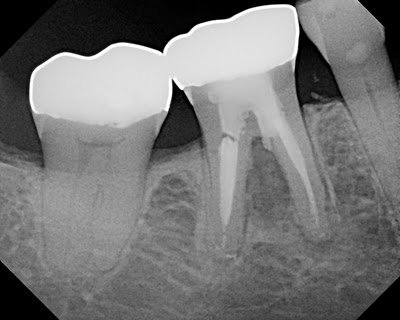

This patient presented for treatment of #30 in March 2009. Prior RCT had been done and a large furcal lesion as well as periapical lesion were noted. Retreatment was recommended. Upon access, we found 2 additional canals as well as a furcal perforation. The tooth was obturated and perforation was repaired using MTA.

Post-Op films shows the MTA repair in the furcal area. Note the large lesion around the mesial root.